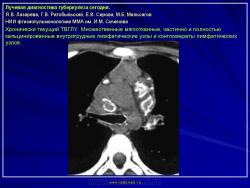

Лучевая диагностика туберкулеза сегодня

Я.В. Лазарева, Г.В. Ратобыльский, Е.В. Серова, М.Б. Мальсагов

НИИ фтизиопульмонологиии ММА им. И.М. Сеченова